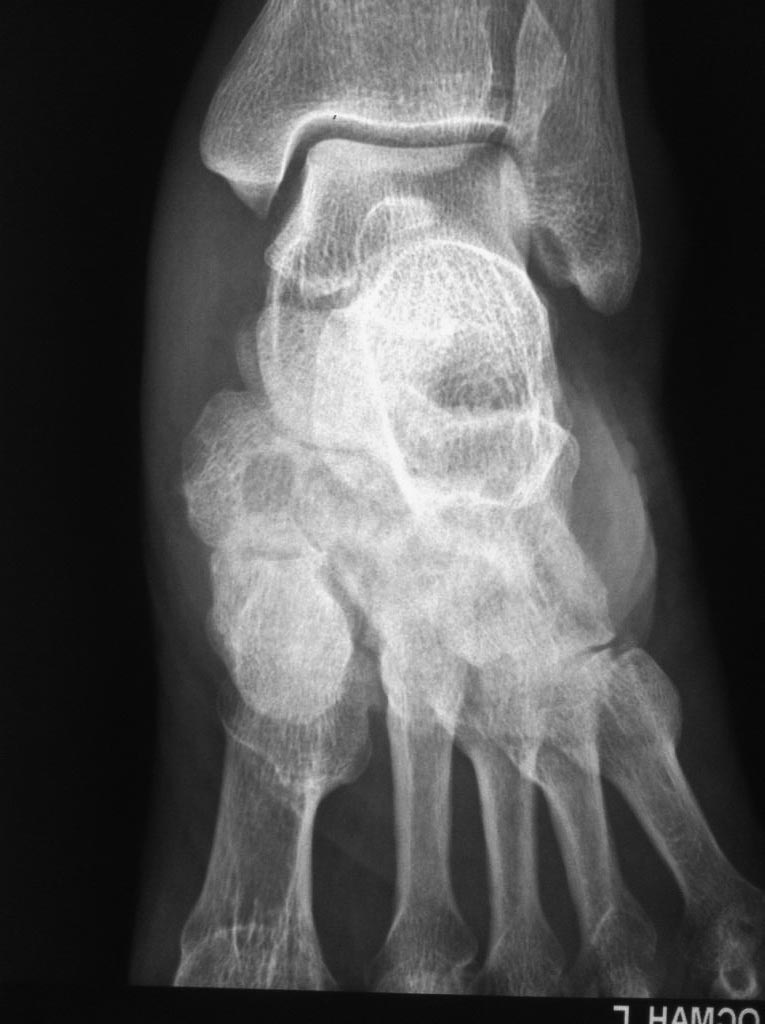

Асептический некроз костей среднего отдела стоп.

Доброго времени суток. Обратился пациент, 62 года, бытовые и трудовые условия в данное время не отягощены и не были никогда тяжелыми, без вредных привычек,

со слов оперативных вмешательств не было, курсов гормональной терапии не получал, периодически принимает лекарственные препараты от арт. гипертензии. Без видимых причин около 1 года назад появились боли в стопах при ходьбе и нагрузке, в связи с чем обратился к ортопеду.

Лаб исследования: Ревмофактор, С-реакт. белок, АЦЦП, Мочевая кислота и др. в пределах возрастной нормы. Хотелось бы услышать мнения. Заранее благодарен.

Добрый день. Похоже на Charcot

И, забыл добавить, есть мнение, что ингибиторы АПФ, например эналаприл, эту саму артропатию Шарко могут вызывать.